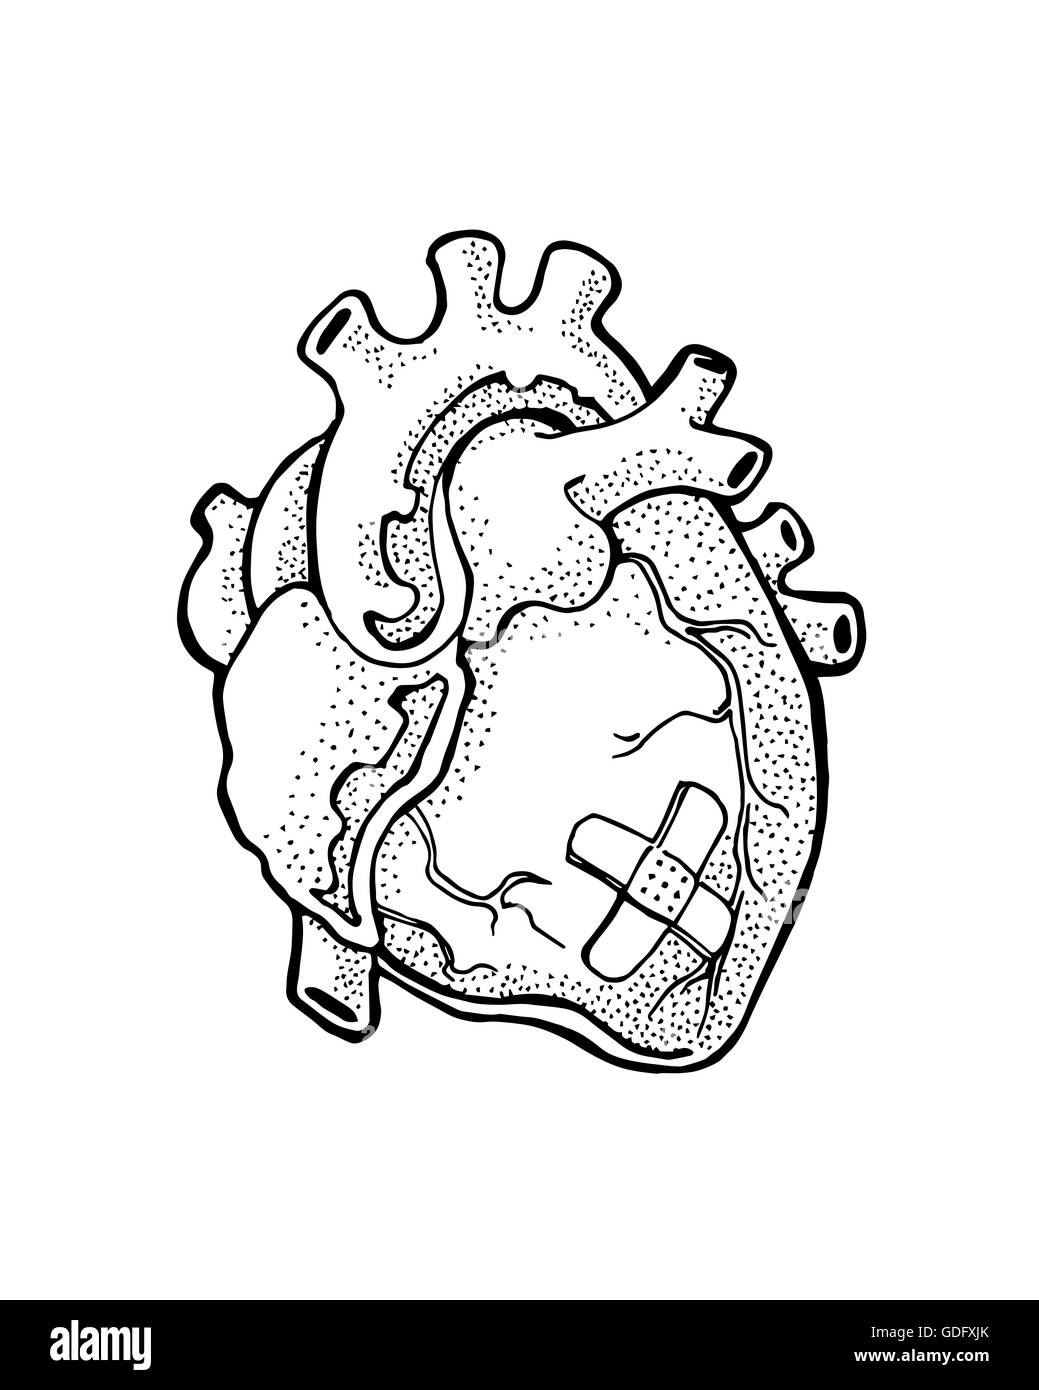

37+ black and white diagram of the heart

664 Human Heart Black And White Photos And Premium High Res Pictures Getty Images

Human Heart Black And White Stock Photos Images Alamy